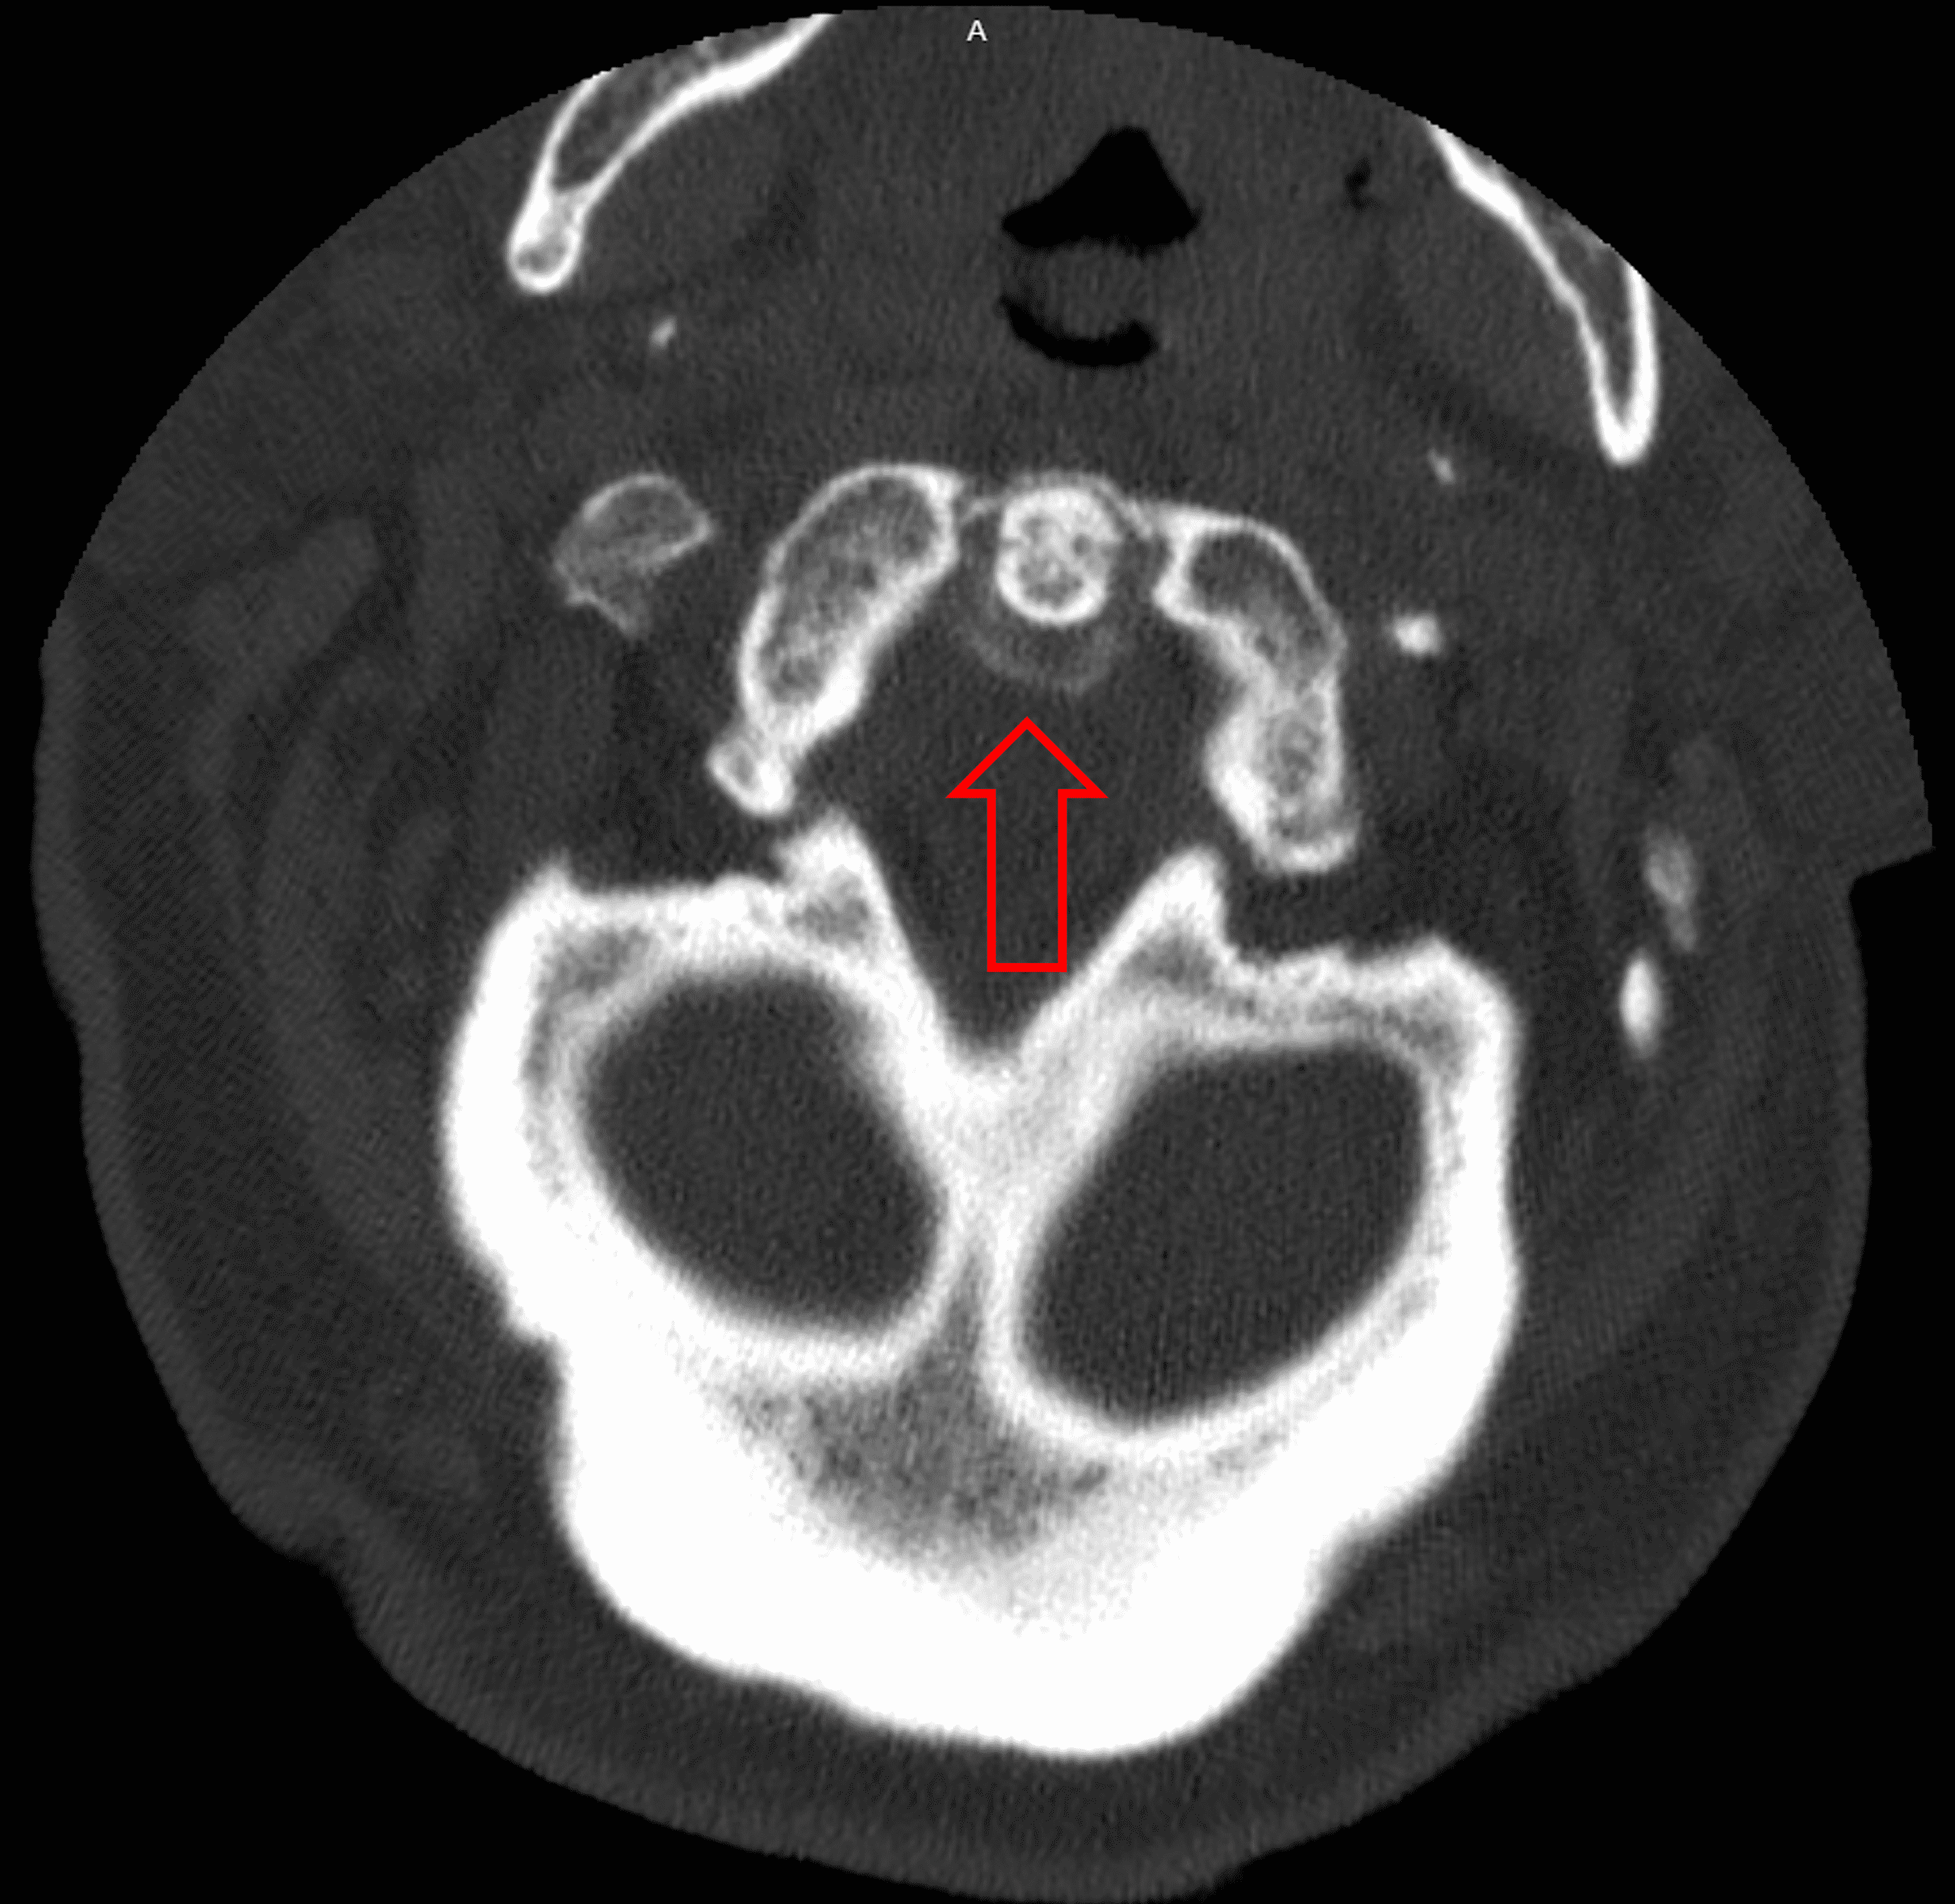

Cervical CT scans around the odontoid process (dens). a The axial image What Is A Dens Process Learn about its role in motion, how it can be injured by trauma or. The odontoid process, or dens, is a bone that connects the atlas and axis vertebrae in the neck. Learn about its anatomy, function and types of fractures, with images and references. The odontoid process (or dens) is a projection of the second cervical vertebra that articulates. What Is A Dens Process.

Cureus Crowned Dens Syndrome A Rare Complication of Calcium

Cureus Crowned Dens Syndrome A Rare Complication of Calcium What Is A Dens Process Lets take a quick look at one type of neck injury called an odontoid fracture, aka a den's fracture. Learn about odontoid fractures, the most common fractures of the axis (c2) dens, and their classification, diagnosis, and treatment. Crowned dens syndrome is a rare condition that occurs when calcium deposits form on the odontoid process, a bone that connects the. What Is A Dens Process.